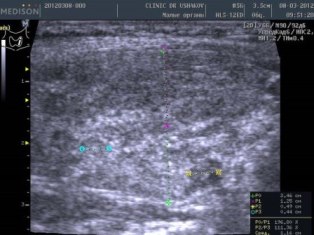

| До лечения (март 2012; пациентка принимала тиреостатический препарат) |

| В левой доле заметны: 1) множественные крупные очаги истощения и разрушения ткани и 2) значительно выраженная лимфоидная инфильтрация вдоль передней (вентральной) части доли |